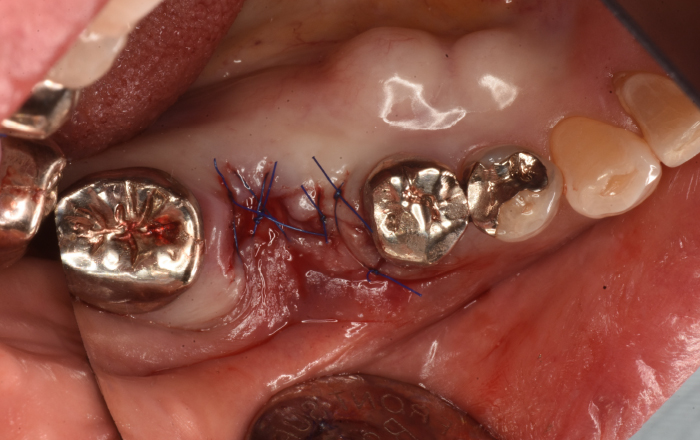

歯根分割(歯の根の股のところの骨吸収に対する処置)

このように歯の根の股のところの骨が歯周病で吸収しており、排膿(膿がでること)しています。歯ブラシ、歯間ブラシが届かないことが一つの原因です。

重度歯周病

手術的に歯を分割して、清掃器具が入る隙間を確保します。

最終的にセラミックで修復し、清掃器具が確実に入るようにします。

横からみたところです。